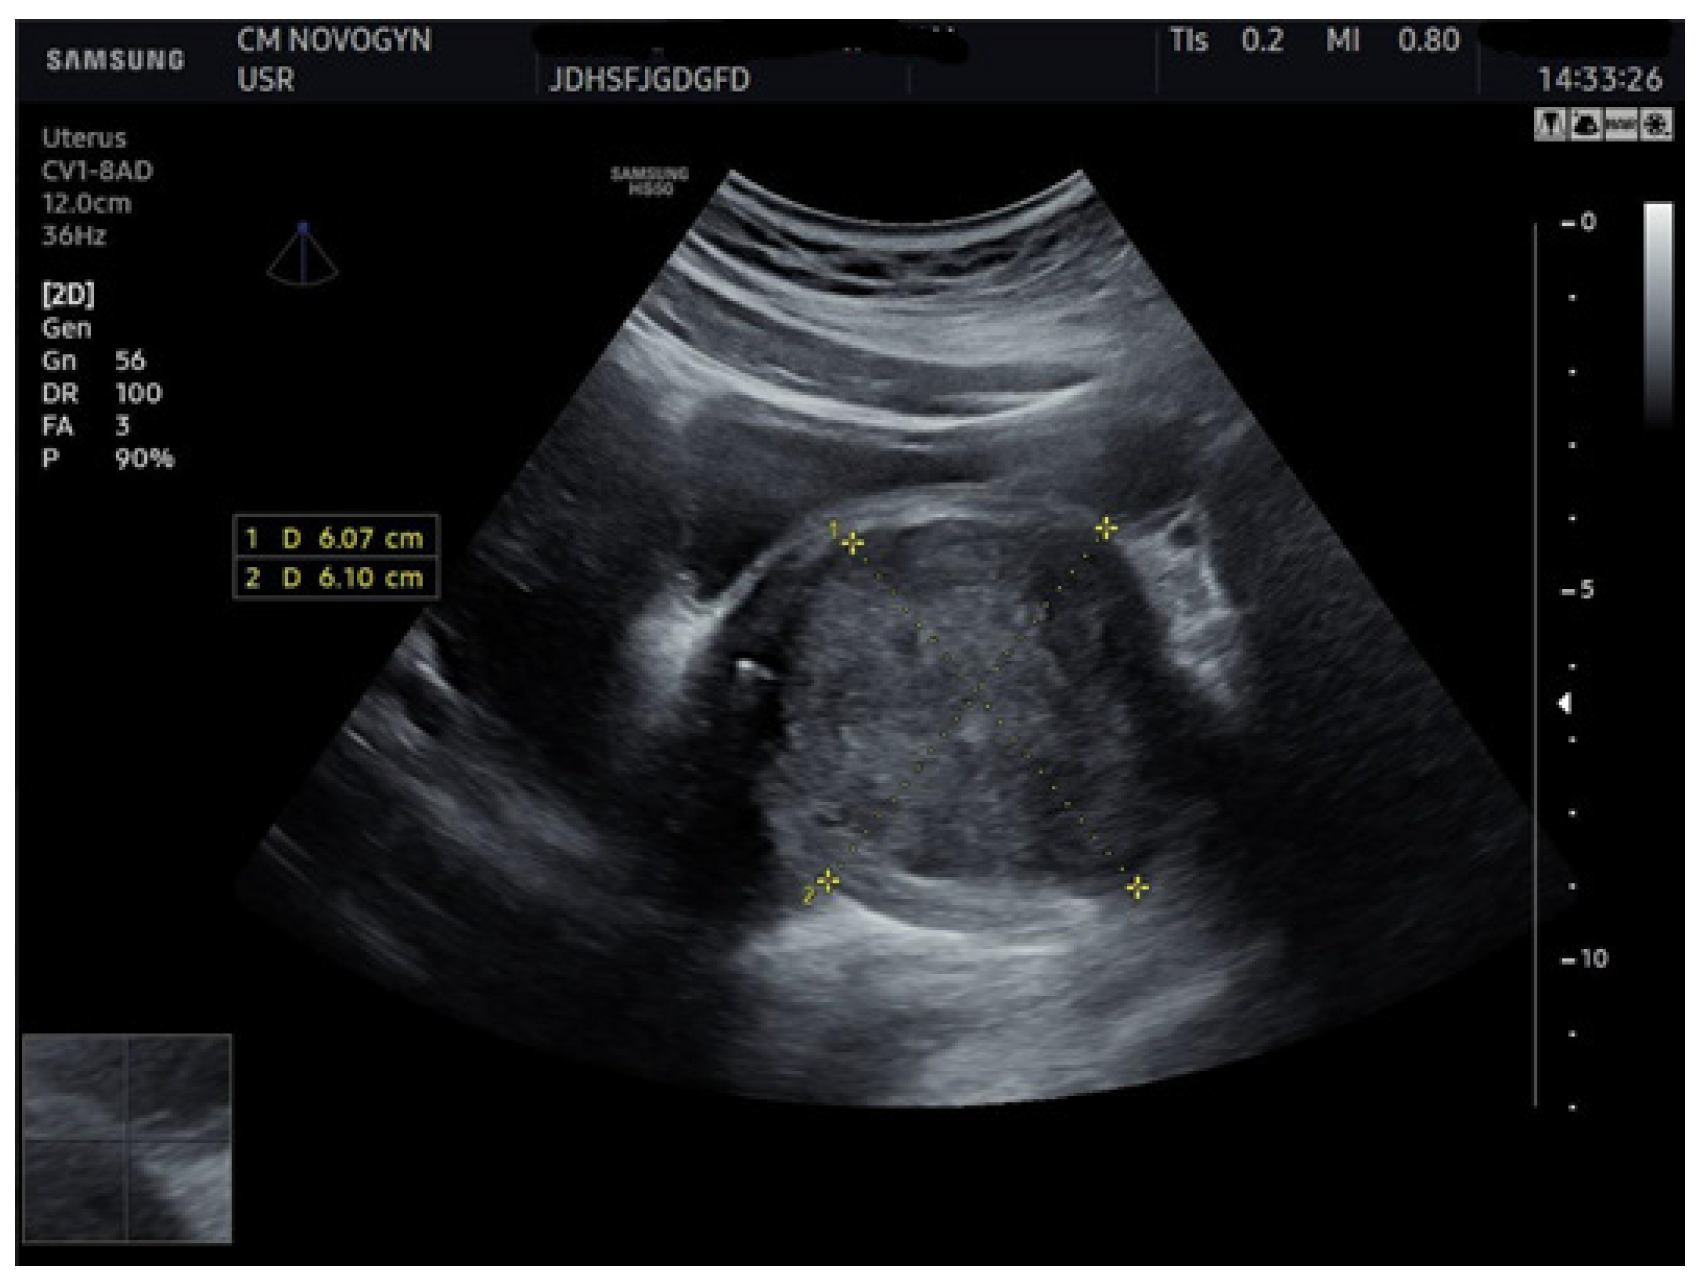

Additional abdominal ultrasonography confirmed a well-circumscribed mass measuring 6.07 × 6.10 cm from alternative imaging planes, demonstrating consistency with initial findings (Figure 2).

Figure 2.

Abdominal ultrasonographic image visualizing the well-demarcated, solid, hypoechoic mass (calipers) in the vesicovaginal region measuring (6.07 × 6.10) cm, confirming a consistent solid nature.